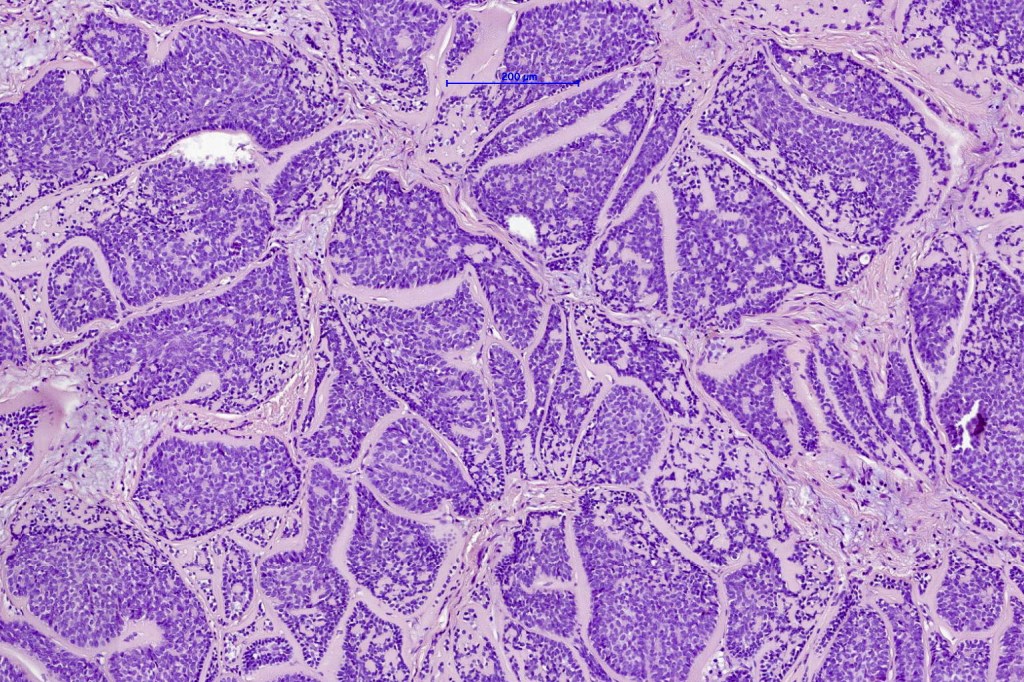

Histological features

•Dermal based

•Jigsaw/mosaic pattern arrangement of variably sized lobules of tumor cells with surrounding think, eosinophilic hyaline basement membrane

•Intralobular hyaline basement membrane material droplets

•Outer layer of intensely basophilic small cells surrounding larger central cells with pale staining or eosinophilic cytoplasm & vesicular nuclei

•Ductal differentiation